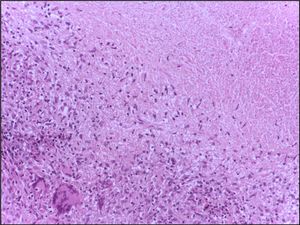

라이트 염색된 Blood film|말초 혈액 도말 표본영어을 현미경으로 보면, 정상적인 림프구는 크고 어둡게 염색된 핵을 가지며, 호산성세포질은 전혀 없거나 거의 없다. 정상적인 상태에서 림프구의 거칠고 밀집된 핵은 적혈구의 크기와 비슷하다(직경 약 7μm).[13] 일부 림프구는 핵 주위에 뚜렷한 핵 근방 영역(헤일로)을 보이거나, 핵의 한쪽에 작고 뚜렷한 영역을 보인다. 폴리리보솜은 림프구의 두드러진 특징이며, 전자 현미경을 사용하여 볼 수 있다. 리보솜은 단백질 합성에 관여하며, 이러한 세포에서 다량의 사이토카인 및 면역글로불린의 생성을 가능하게 한다.[13]